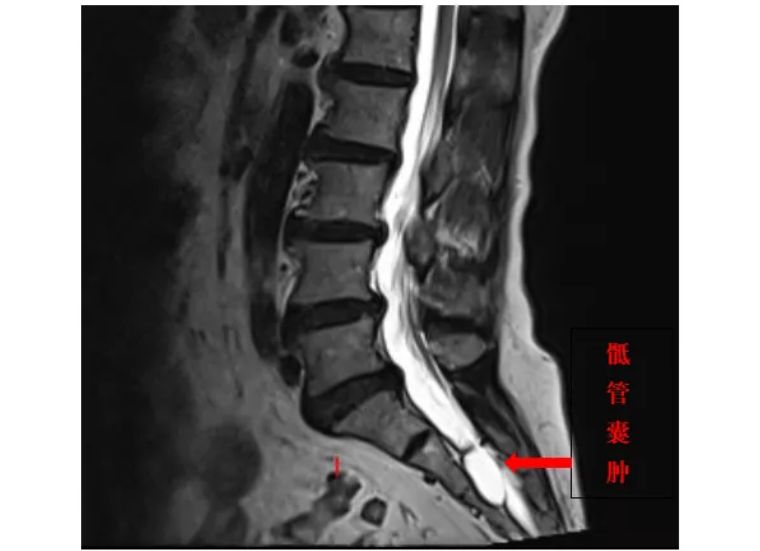

娄永利主任详细了解病情后,建议孟阿姨做一个腰骶部磁共振成像,结果显示,孟阿姨患有骶管囊肿。

骶管囊肿造成了脊髓的紧张,

从而引起孟阿姨的一系列症状。